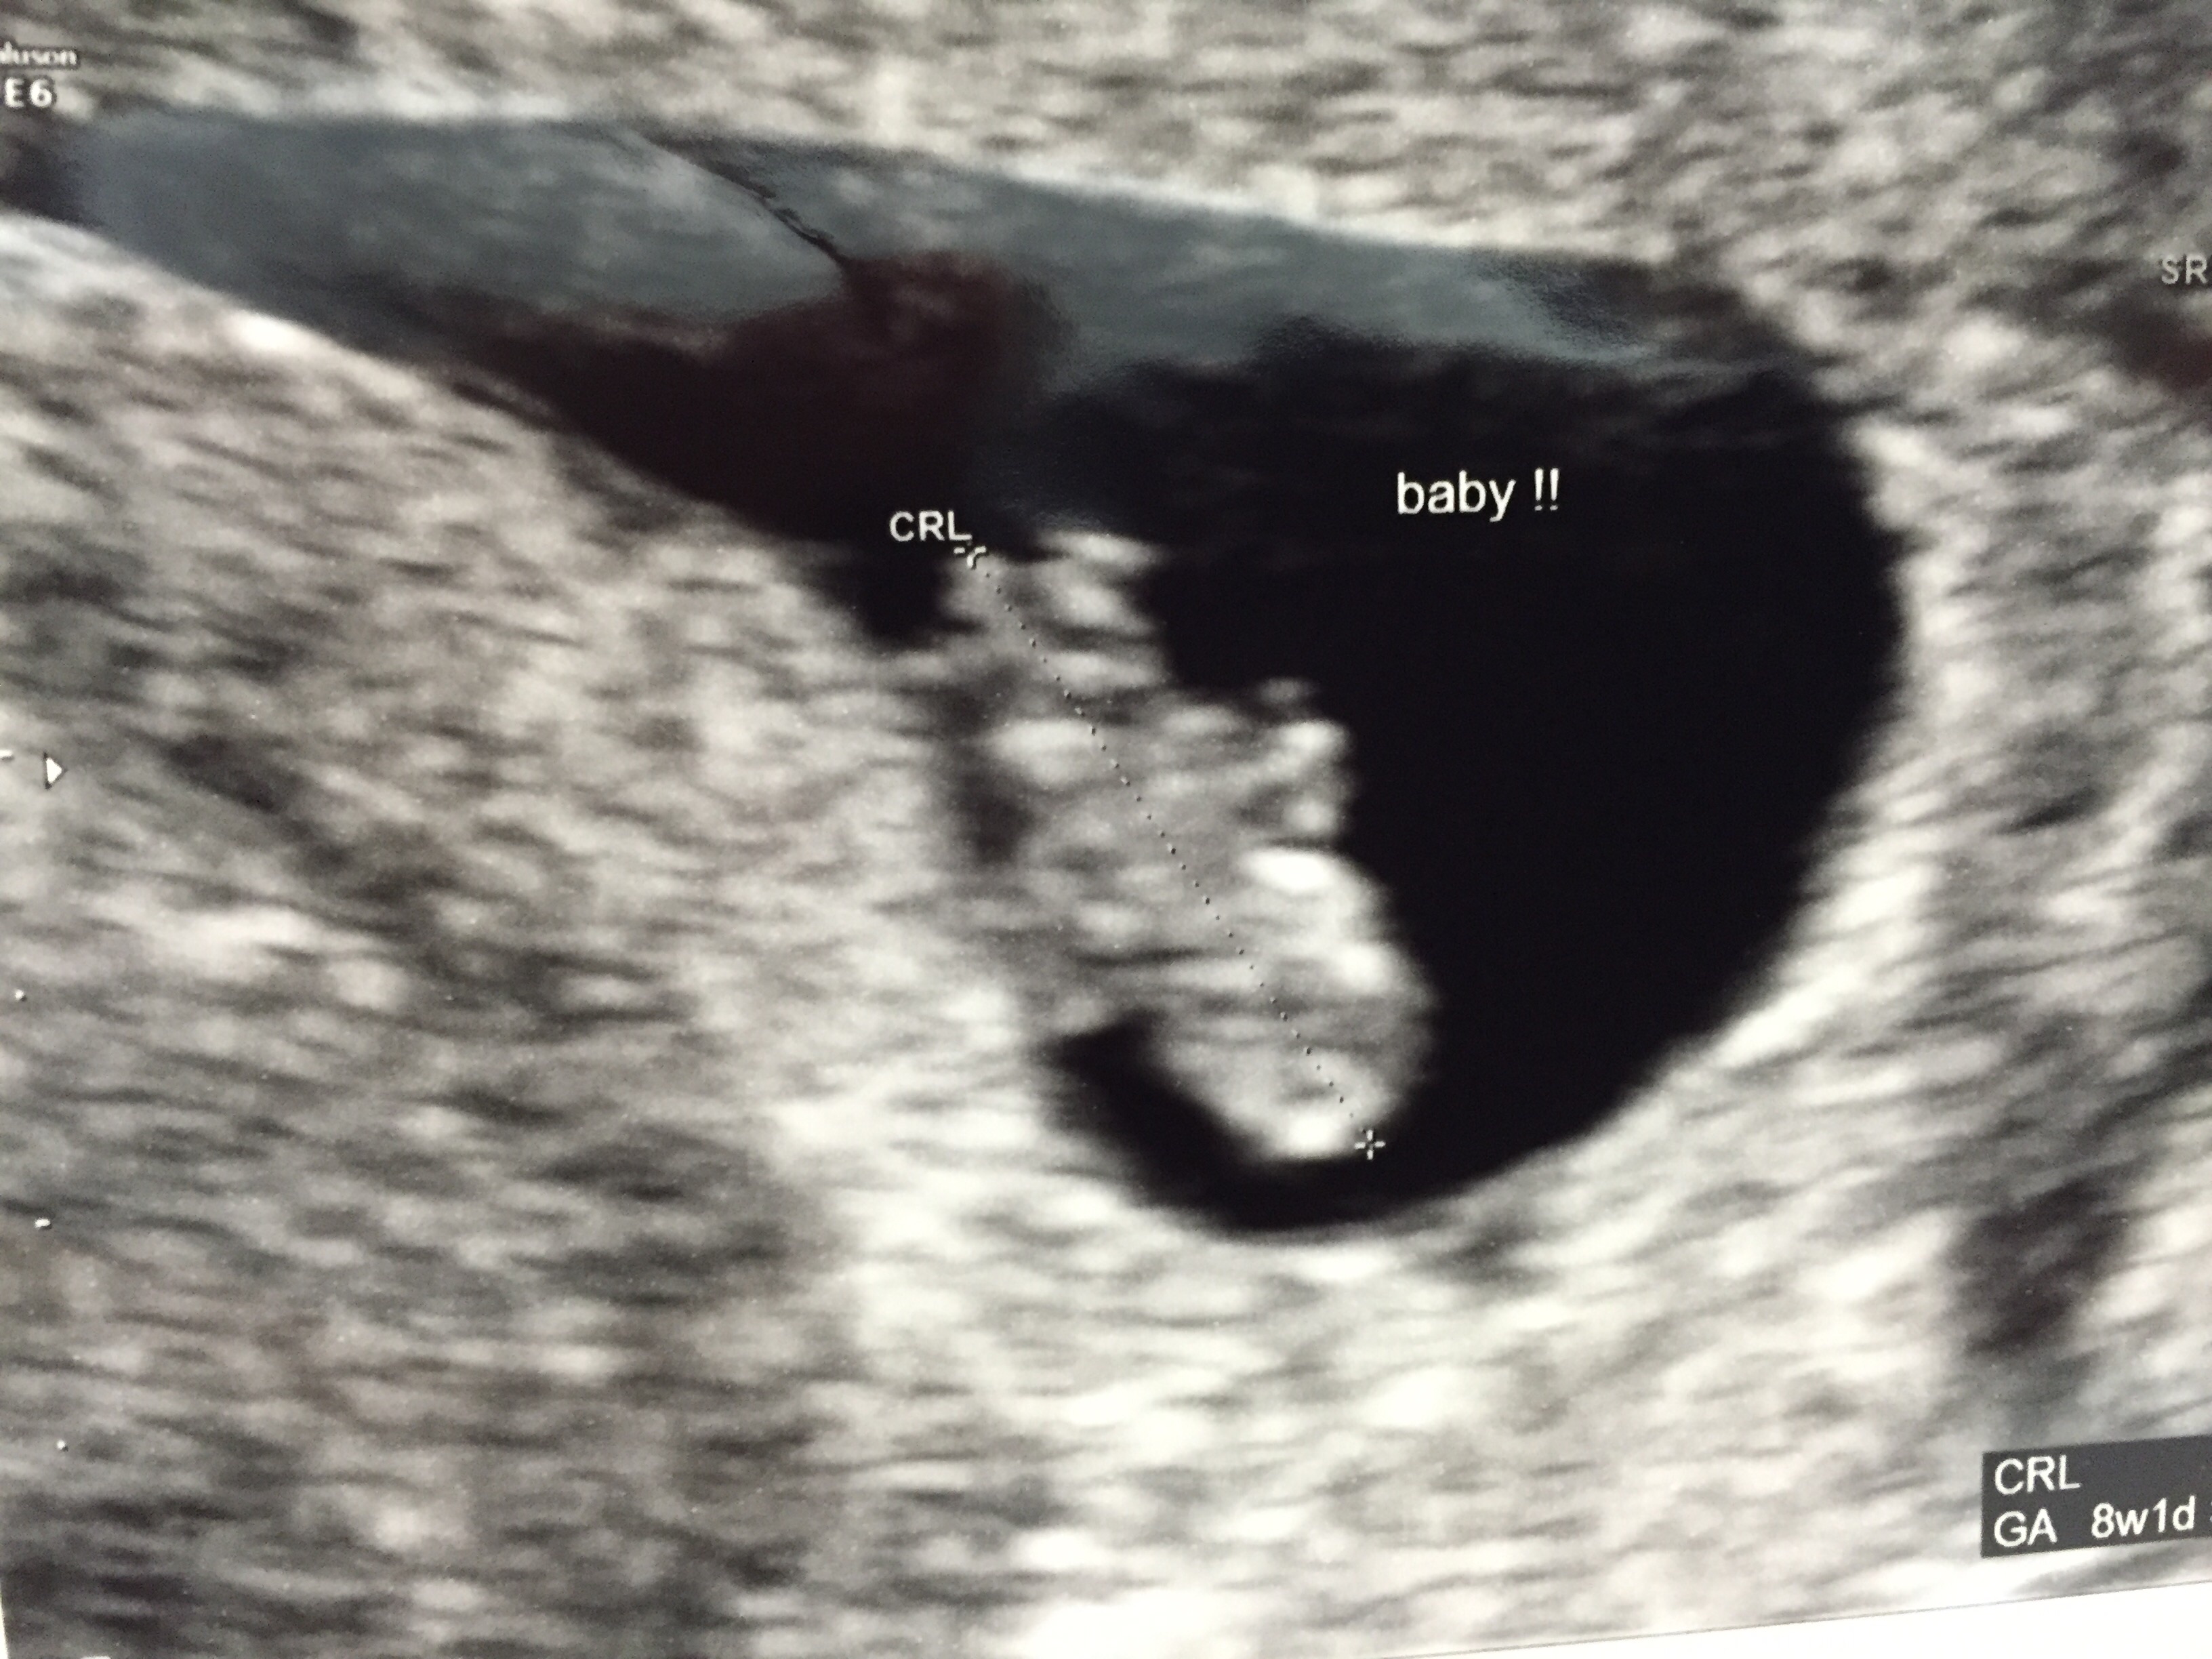

I go tomorrow for my 8 week appointment. It will be my third ultrasound (had a minor freak out yesterday when I had NO symptoms and they got me in for a quick check for a heart beat to stop my panicking and then one at 6 weeks as well), but first appointment with my doctor. I am still super nervous though... It was at this appointment when we learned our first had no heart beat and had stopped growing. Trying to stay positive and excited to get another picture of the little peanut!!

Appointment went well today! Baby continues to grow and has a strong heartbeat. My ob was great too- said that I can come in every 2 weeks instead of every 4 weeks (at least for the next few appointments) so that I don't get so nervous between appointments. I included a picture of our little one- a little blurry, but a baby!! Crazy how small it is!!

We had a great appointment. We are at 8w3d. I cried as soon as we heard the heartbeat. I'm so relieved. I go back in two weeks for a feel good check up. From here on out it's uncharted territory. I'm glad to be past my milestone mark.